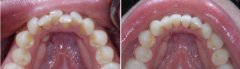

牙齿不齐怎么矫正?

看到明星一口整齐靓丽的牙齿,是否羡慕不已。随着现代医疗技术的进步,牙齿...【详细】

美容修复牙齿不齐哪里好?

牙齿东歪西倒是牙齿畸形的表现,对于这种现象,有很多患者都表示过不想做全...【详细】